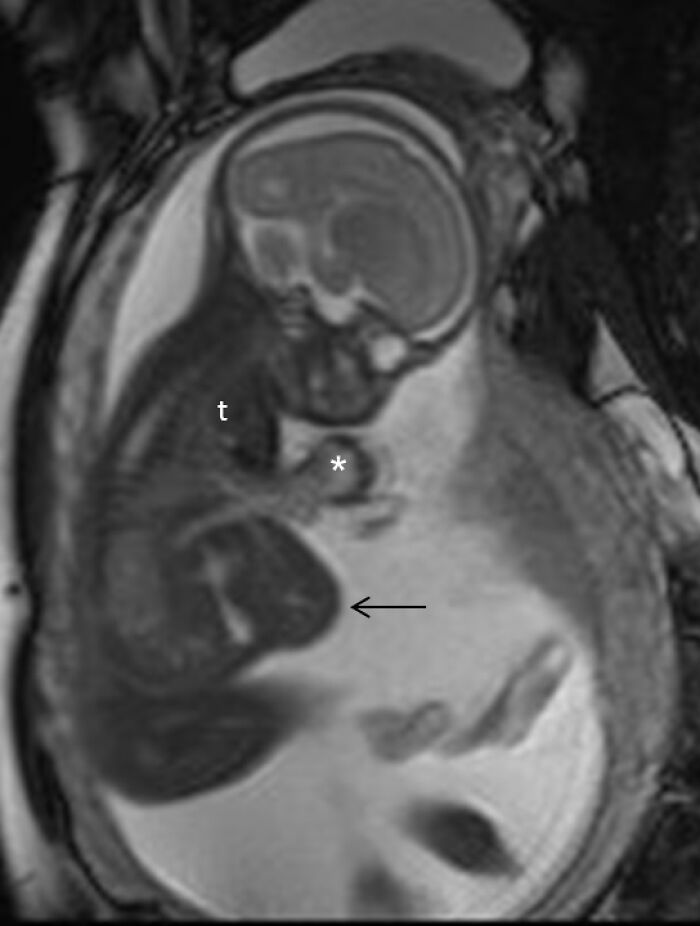

Fetus-in-fetu. 10 year old boy "pregnant" with his parasitic twin (PT).

Edit:

Case

10 y.o. boy came in with enlarging abdominal mass and intermittent generalized weakness. Imaging revealed a parasitic "fetus" which was also growing in size. History revealed mass noted 2 years ago which enlarged rapidly the last 3-4 months. Within days of admission, boy's organs begin to fail with no apparent reason. He was healthy and eating well when he was admitted. Family wanted surgical intervention to separate the parasitic twin against surgeons' advice. parasitic twin was basically starving/poisoning the boy. Surgeons opened the boy up and found that the boy and parasitic twin share a (stomach, liver, heart, blood vessels - mesodermal organs) basically too complex to operate. The boy passed away after.

This happened to a poor family in a underfunded government hospital in a corruption-infested country. The parasitic twin was donated to the hospital. It had teeth with hairy limbs with the longest curved baby nails. I can't describe it further. It is on display at the Surgeon's Hall.

Edit 2:This happened years ago before the age of smartphones.The hospital team tried to have the tissues studied for academic purposes. there was a case report about it presented in a local medical congress but as this happened in a "third world" country with limited resources, nothing came of it. I live and work in a different country now.